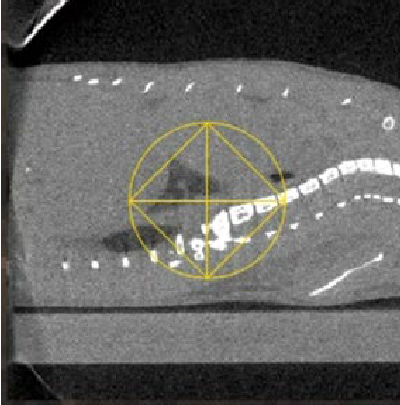

Fig 2. Reconstructed CBCT image of a mouse with lung fibrosis as viewed in the SmART+ software. (Left) Axial, (Center) Sagittal and (Right) Coronal views.